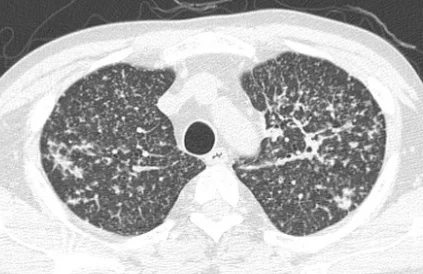

Очаги могут иметь различную природу и быть вызваны множеством причин, от инфекции и воспаления до зарождающейся опухоли или фиброза.

Большинство очагов в легких имеют доброкачественную природу, задача рентгенолога заподозрить неладное, если ему не понравились те или иные очаги.

Некоторые характеристики очагов помогают врачу предположить, о каком именно процессе идет речь. Но, к сожалению, нельзя со 100% уверенностью при первом же осмотре заявить, что этот очаг точно является тем-то или тем-то. Медицина, как известно, наука вероятностей.

5. Структура – кальцинированные или нет

Если нет, то по КТ очаг принято относить к одной из трех групп (так решила международная группа ученых под названием Флейшнеровское сообщество)